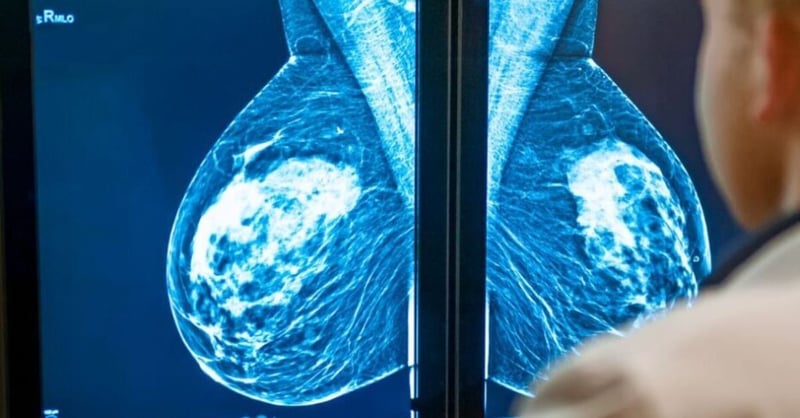

What is a Mammogram?

A mammogram is an X-ray of the breast used to detect and diagnose breast conditions. By offering a detailed view of the breast tissue, it can reveal abnormalities before they become palpable.